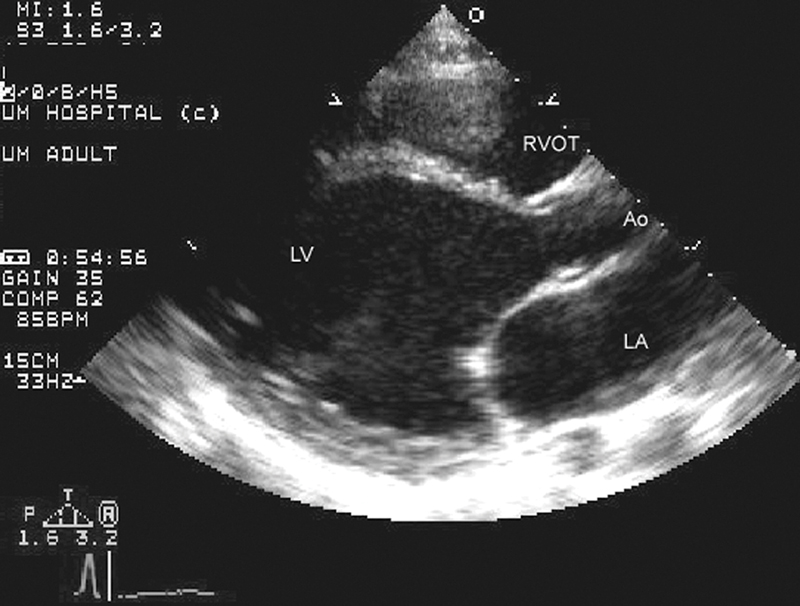

فحوصات تشخيصية لبعض امراض القلب والشرايين التاجية